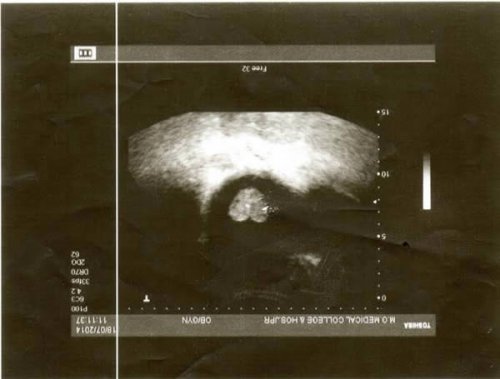

3. Плацента в форме сердца

Плаценты, как правило, обладают круглоовальной формой, однако плаценты необычной формы не являются редкостью.

Согласно данным Кооперативного Перинатального Проекта (Collaborative Perinatal Project), необычные формы плаценты обычно ассоциируются с меньшим весом плода и самой плаценты, что позволяет предположить, что плаценты необычной формы обладают модифицированной функцией.